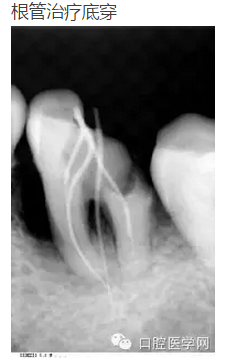

幾張失敗的根管治療x線診斷